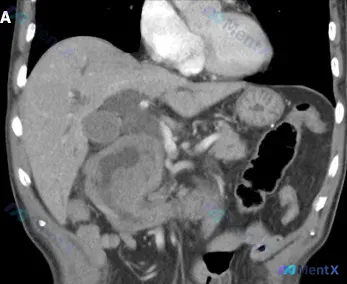

整理了一个很有教育意义的影像病例,从征象到分析逻辑走一遍,希望能给大家提个醒。 --- 影像核心表现 这是一份腹部CT横断面影像: - 定位:腹膜后脊柱前方,腹主动脉旁及左侧 - 形态:边界相对清晰的类圆形/分叶状软组织肿块 - 关键征象: 1. 肿块内部可见多发点状、团块状高密度钙化灶(极亮白区域...